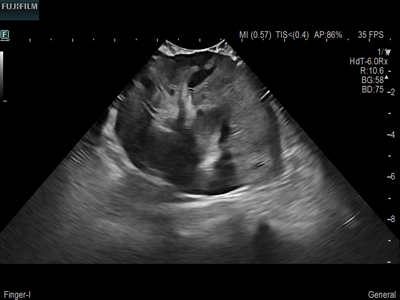

Curved array deep penetration “I” style finger-grip transducer for open kidney surgical procedures. Allows for palpating organs and scanning at the same time.